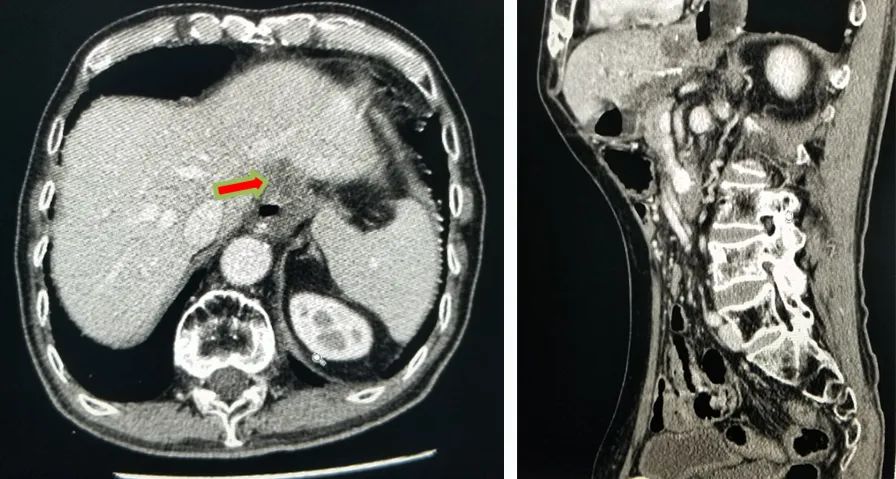

PET-CT检查:1、胃癌大部切除术后改变;肝左外叶近包膜下高代谢结节(于临近胃食管吻合口分界欠清),考虑肝转移。2、右肺中上叶多发结节伴代谢轻度增高;双肺间质纤维化;双肺泡性气肿;经根部气管憩室;贫血;动脉硬化;双侧胸膜增厚;右肺门及纵隔内多发淋巴结增生。

△ 2019.7影像学检查